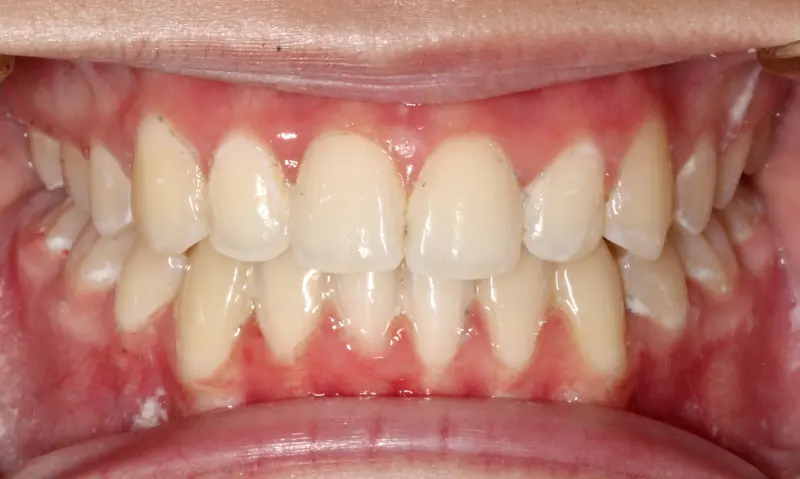

After treatment: The Extraction Myth

After

The Diagnosis

Bimaxillary protrusion (teeth flaring forward) causing lip incompetence. The patient struggled to close his lips comfortably, straining the chin muscle (mentalis).

The Engineering

A strategic extraction plan (4 premolars) allowed us to retract the front teeth. Note the dramatic improvement in chin projection and facial balance. The extractions did not flatten the face; they harmonized it.